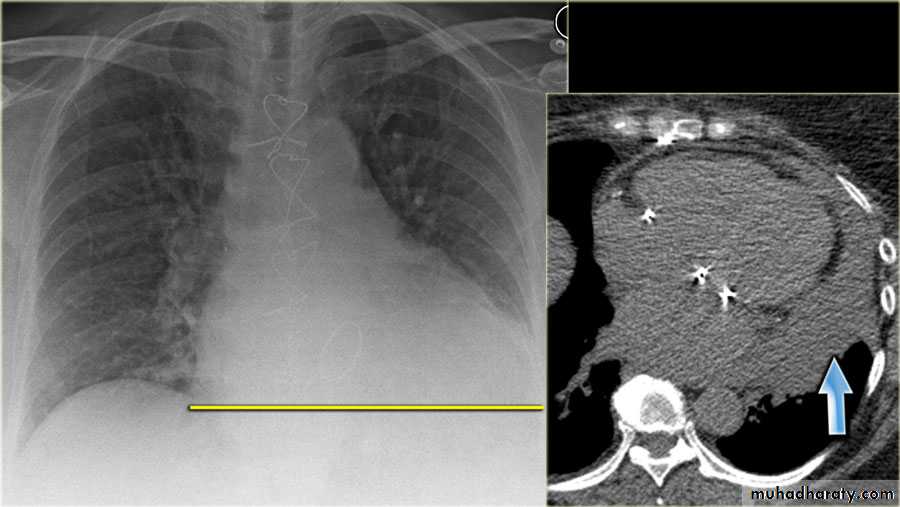

History: dyspnea, weight loss, dehydration with poor immunity